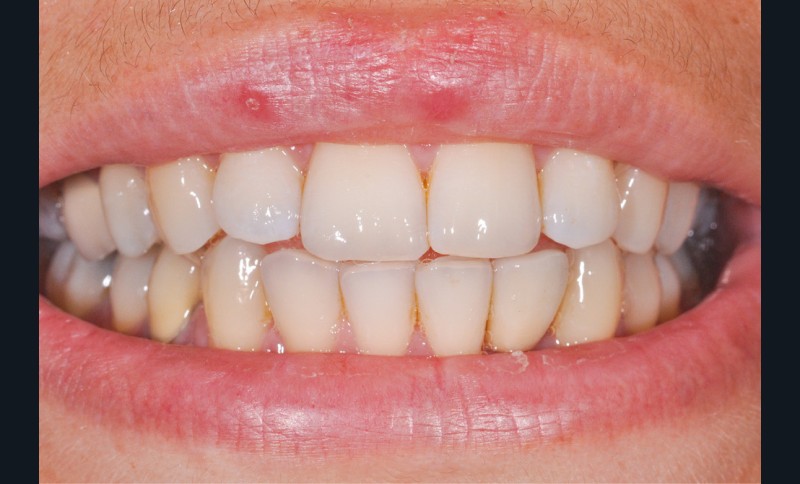

Le scellement de restaurations sur des piliers implantaires demeure une solution très intéressante (fig. 1). Cette technique reprend en effet les standards de la prothèse sur dent naturelle, à savoir un pilier implantaire (faux-moignon) vissé dans l’implant sur lequel est scellée une coiffe prothétique. Ses principaux atouts sont de corriger facilement les axes implantaires s’ils sont divergents par rapport à ceux des couronnes, tout en masquant l’émergence de la vis du pilier et conservant ainsi les faces occlusales intactes.

Ces dernières sont donc aptes à remplir correctement leur rôle d’occlusion, et à préserver la solidité de la céramique en limitant les risques de fracture.